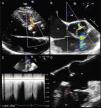

A 36-year-old man was referred to our hospital for a recent finding of a heart murmur. He had no relevant medical history except paroxysmal palpitations in the previous three months. Physical examination revealed a high-grade continuous rumbling murmur best heard at the left sternal border. Initial transthoracic echocardiography showed continuous flow between the aorta and the right ventricle (RV) (Figure 1A). The subsequent transesophageal echocardiogram (TEE) confirmed the presence of a tubular, windsock-like communication 4.5 mm in diameter between the right sinus of Valsalva (RSV) (displayed deformed) and the RV (Figure 1B and 1D, Video 1), with an effective regurgitant orifice of 0.11 cm2 in color flow Doppler (according to proximal isovelocity surface area measurement) and a systolic-diastolic flow in continuous wave Doppler (Figure 1C). There was also moderate aortic regurgitation (grade 3/4), with an eccentric jet directed toward the anterior mitral leaflet. Real-time three-dimensional (RT3D) TEE demonstrated the tubular morphology of the ruptured sinus (enlarged) and the direction of flow described above (Figure 2A and B, Video 2). Finally, multiplanar reconstruction color flow three-dimensional TEE showed a vena contracta area calculated by direct planimetry of 0.09 cm2 (Figure 2C). The patient underwent surgical defect closure with monofilament suture, leaving mild aortic regurgitation on intraoperative TEE.

(A) Transthoracic color Doppler echocardiography, parasternal long axis view, showing a continuous flow from the aorta to the right ventricle (arrow). (B) Transesophageal color Doppler echocardiography, mid-esophageal plane at 51°, showing the jet of the fistula (arrow) and moderate eccentric aortic regurgitation. (C) Continuous wave Doppler showing systolic-diastolic flow at the fistula level (arrow). (D) Transesophageal echocardiography, mid-esophageal plane at 124° (zoomed in on the aorta), showing a tubular communication between the right sinus of Valsalva and the right ventricle (arrow). Ao: aorta; LA: left atrium; LV: left ventricle; RA: right atrium; RV: right ventricle.